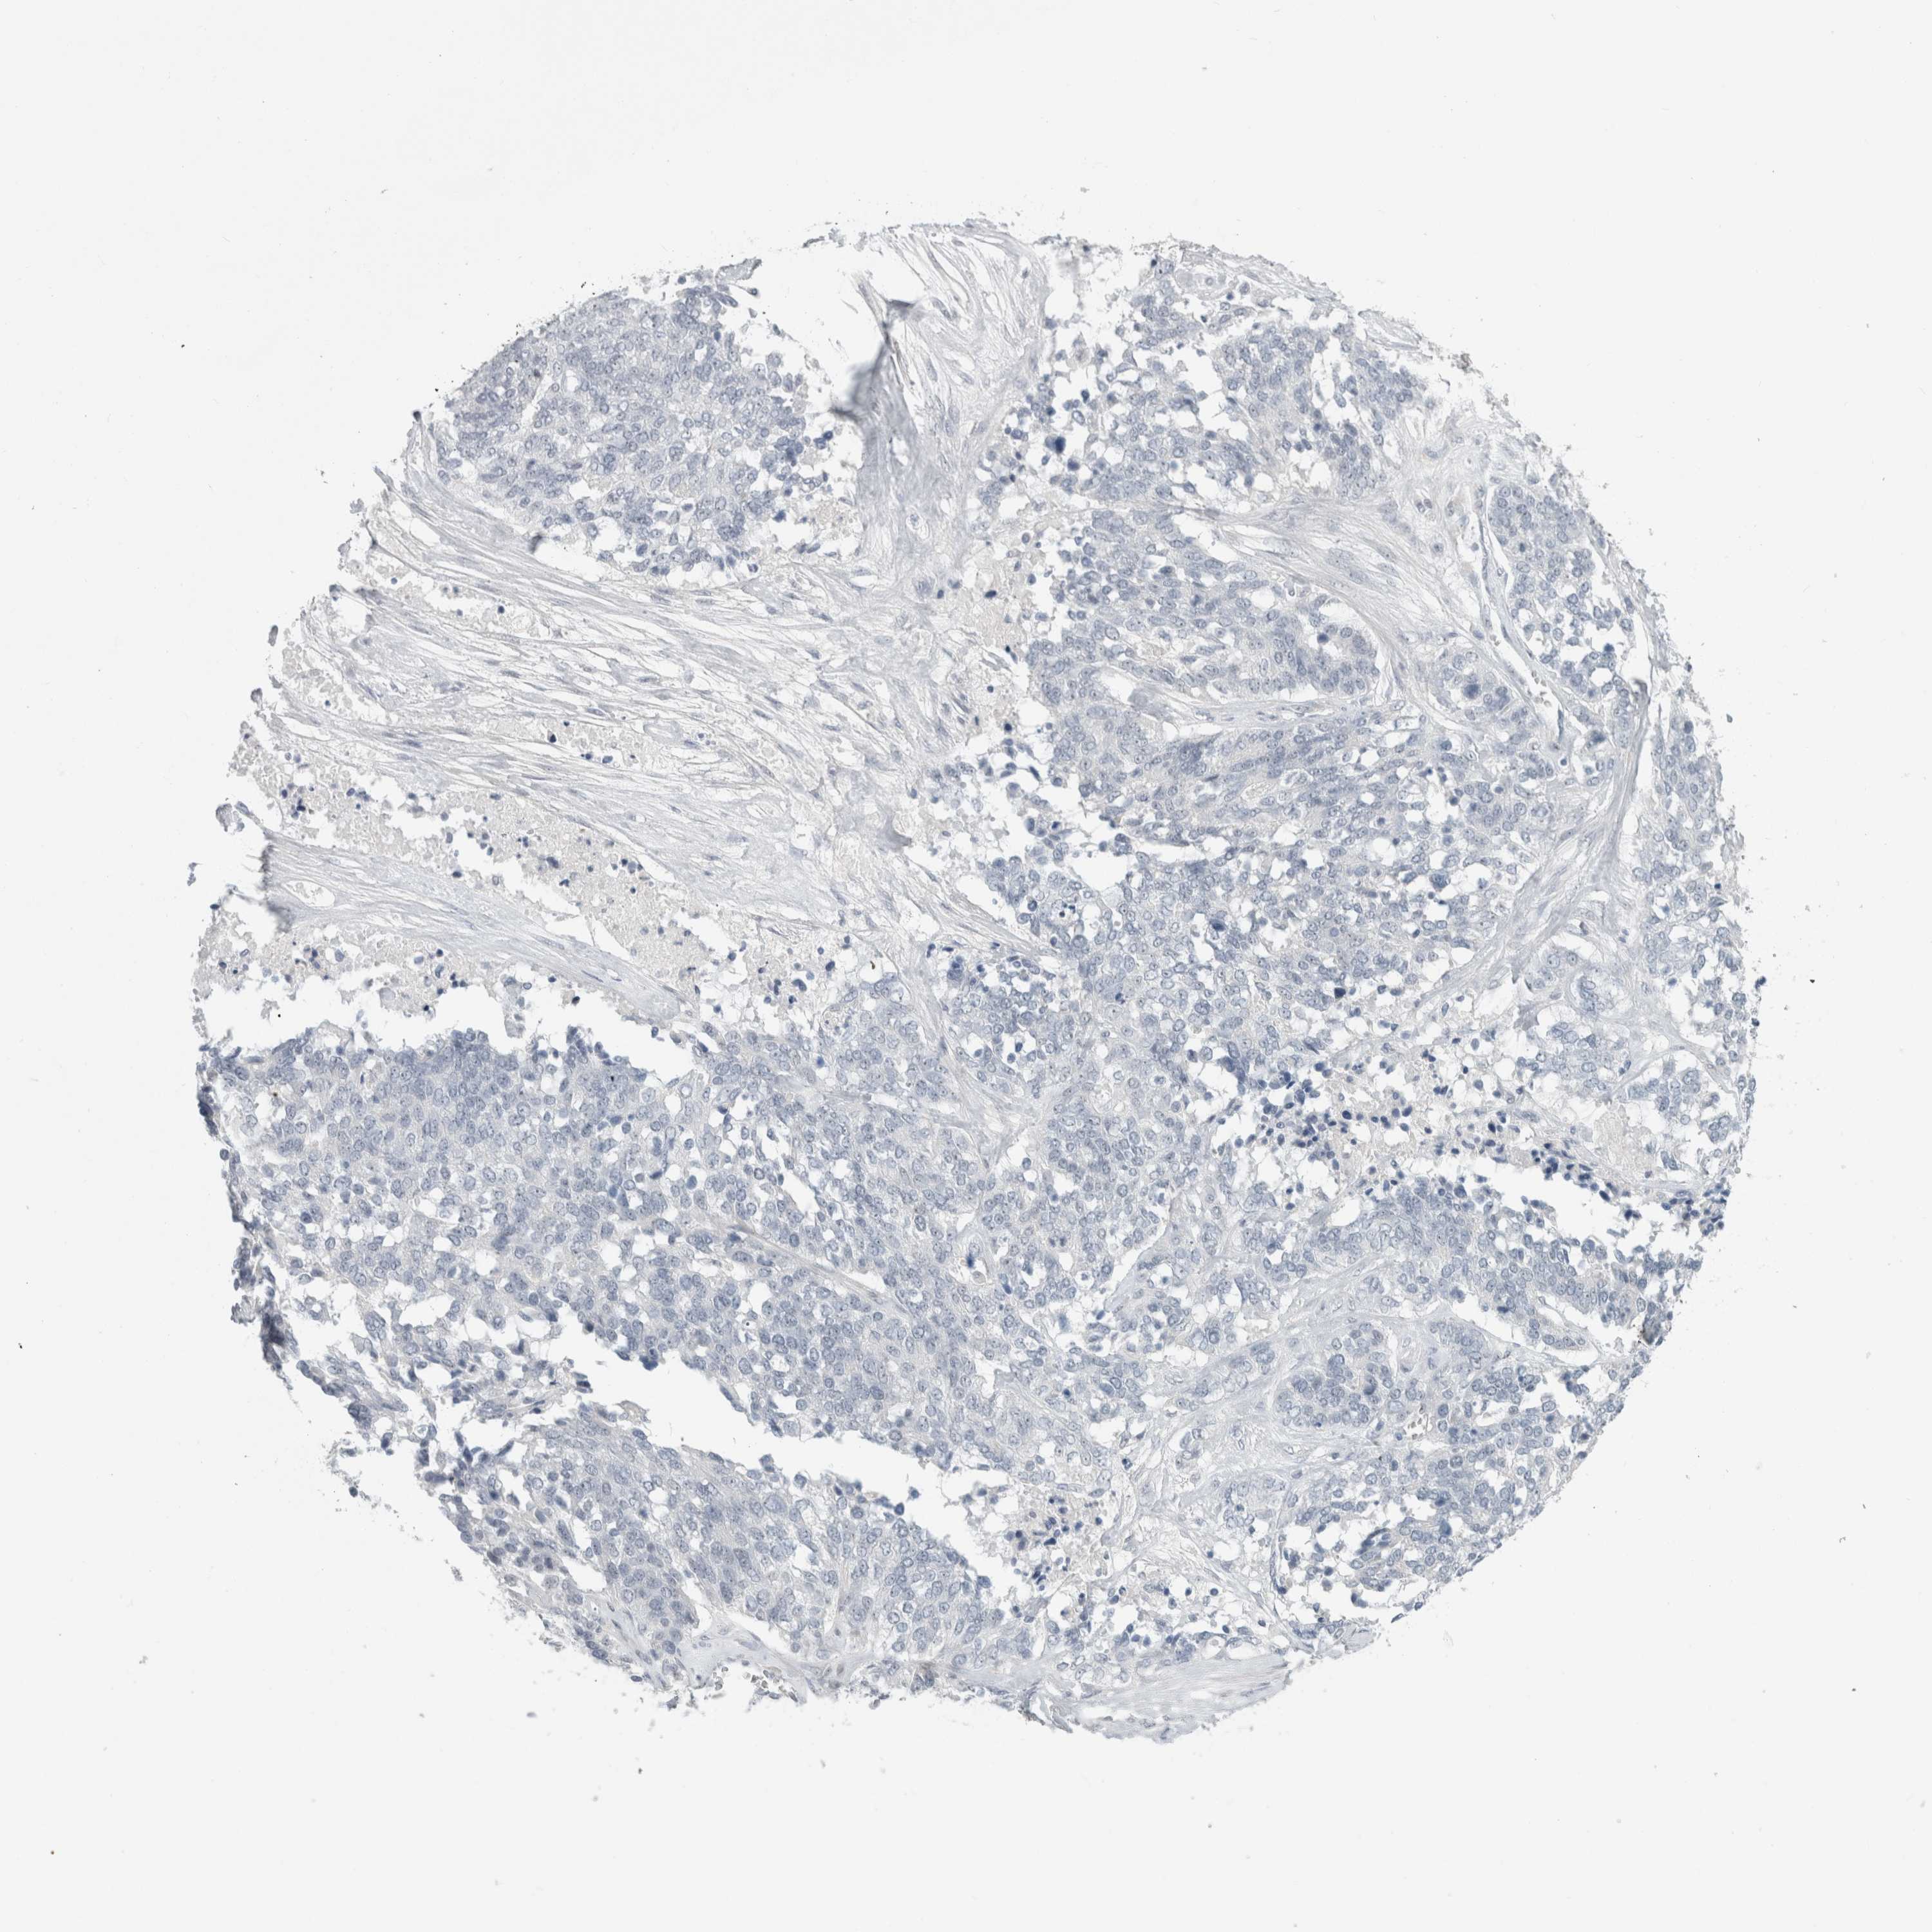

OVARIAN CANCER - Protein expressioni

A mouse-over function shows sample information and annotation data. Click on an image to view it in a full screen mode. Samples can be filtered based on level of antibody staining by selecting one or several of the following categories: high, medium, low and not detected. The assay and annotation is described here.

Note that samples used for immunohistochemistry by the Human Protein Atlas do not correspond to samples in the TCGA dataset.

Antibody stainingi

Antibody staining in the annotated cell types in the current human tissue is reported as not detected, low, medium, or high, based on conventional immunohistochemistry profiling in selected tissues. This score is based on the combination of the staining intensity and fraction of stained cells.

Each image is clickable and will lead to virtual microscopy that enables deeper exploration of all samples and also displays staining intensity scores, fraction scores and subcellular localization as well as patient and tissue information for each sample.

Antibody HPA011284

Antibody CAB026403

Staining

High

Medium

Low

Not detected

Intensity

Strong

Moderate

Weak

Negative

Quantity

>75%

75%-25%

<25%

None

Location

Nuclear

Cytoplasmic/membranous

Cytoplasmic/membranous,nuclear

Cystadenocarcinoma, serous, NOS

Carcinoma, endometroid

Cystadenocarcinoma, mucinous, NOS

Carcinoma, NOS